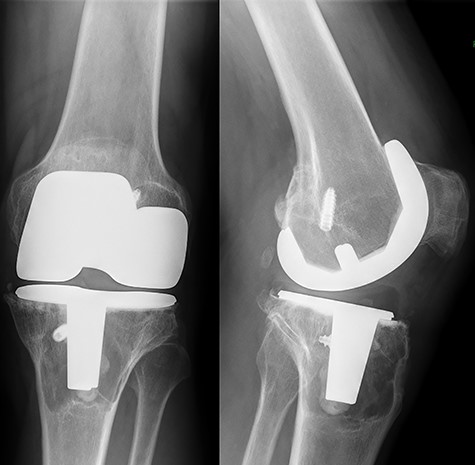

A cemented cobalt–chromium alloy knee arthroplasty from the anatomically graduated components V2 system (Biomet, Warsaw, IN, USA) was implanted using Palacos R + G cement (Heraeus Medical GmbH, Wehrheim, Germany). The one-piece design of the tibial component includes a fixed polyethylene bearing that is molded to the cobalt chromium baseplate during the manufacturing process. During surgery, after resection of the tibial plateau, the tibial titanium interference screw was observed and left in place since it did not interfere with correct placement of the tibial stem. Postoperative recovery went uneventful. Seven years postoperatively, the patient was referred to the outpatient department of our institution complaining of pain on the anteromedial side of the proximal tibia. Previous history included a papillary urothelial carcinoma that was curatively treated 2 years earlier, and a recent discovery of a carcinoma in situ of the bladder was yet to be treated. On physical examination, no signs of effusion and a good range of motion with a flexion of 130° and full extension were present. There was a thickening of the soft tissue present over the anteromedial side of the proximal tibia, which was painful on palpation. Axial load was painful. An X-ray of the left knee showed the titanium interference screw in direct contact with the tibial stem of the prosthesis (see Fig. 1). Additional imaging consisted of a computed tomography (CT) scan and Technetium99 bone scintigraphy. Both revealed a large lytic, sclerotic enlined, lesion surrounding the tibial stem. The direct contact between the interference screw and the tibial stem was confirmed by CT. Serum inflammatory markers were normal as well as serum levels of cobalt and chromium. Diagnosed with aseptic loosening of the tibial component, the patient was scheduled for revision surgery.

Preoperative standing X-ray of the left knee. A large lytic lesion is seen surrounding the tibial component.